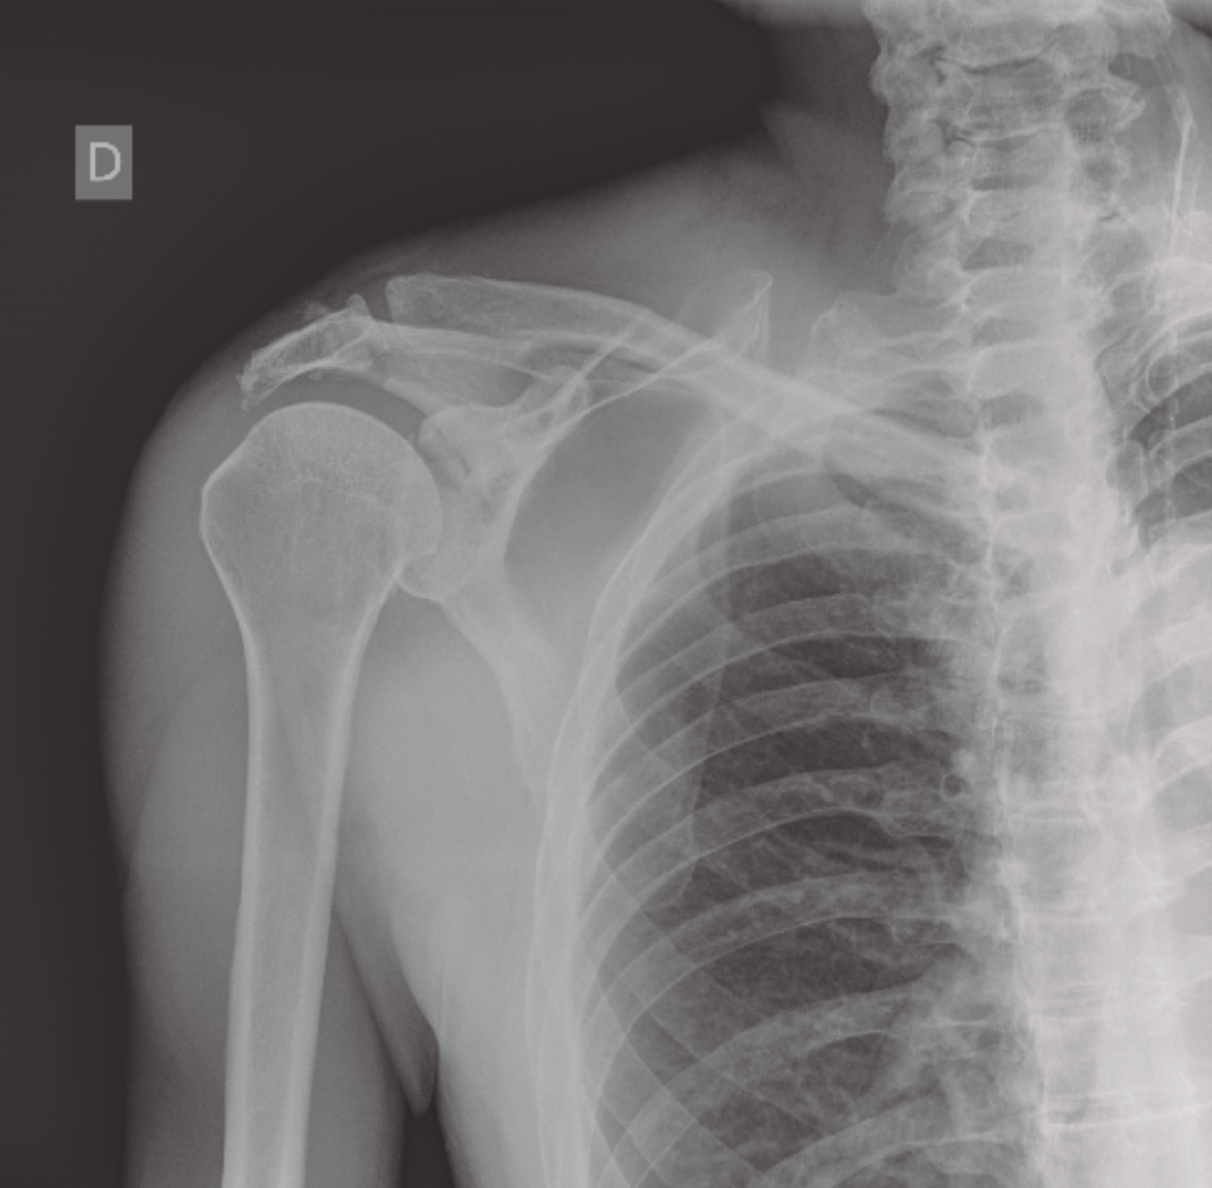

El complejo suspensorio superior del hombro es un anillo óseo y de tejidos blandos formado por el rodete glenoideo, la coracoides, el ligamento coracoclavicular, la porción distal de la clavícula, la articulación acromioclavicular, el ligamento coracoacromial y el acromion. La lesión de dicho anillo a 2 niveles supone una alteración biomecánica importante, que requiere tratamiento quirúrgico dado el potencial de inestabilidad que supone la disrupción del complejo suspensorio del hombro. Presentamos el caso de un paciente que sufrió fractura del acromion y de la cavidad glenoidea con desplazamiento significativo. Tras la estabilización del paciente se procedió a la osteosíntesis de la glena y el acromion con tornillos mediante un abordaje deltopectoral.

The superior shoulder suspensory complex is a bone and soft tissue ring formed by the glenoid cavity, the coracoid, the coracoclavicular ligament, the distal portion of the clavicle, the acromioclavicular joint, the coracoacromial ligament and acromion. The lesion of the ring at 2 levels implies an important biomechanical alteration, which requires surgical treatment because of the potential for instability that involves the disruption of the superior shoulder suspensory complex. We present the case of a patient who suffered a fracture of acromion and glenoid cavity with significant displacement. After stabilization of the patient, osteosynthesis of the glena and acromion with screws was performed using a deltopectoral approach.